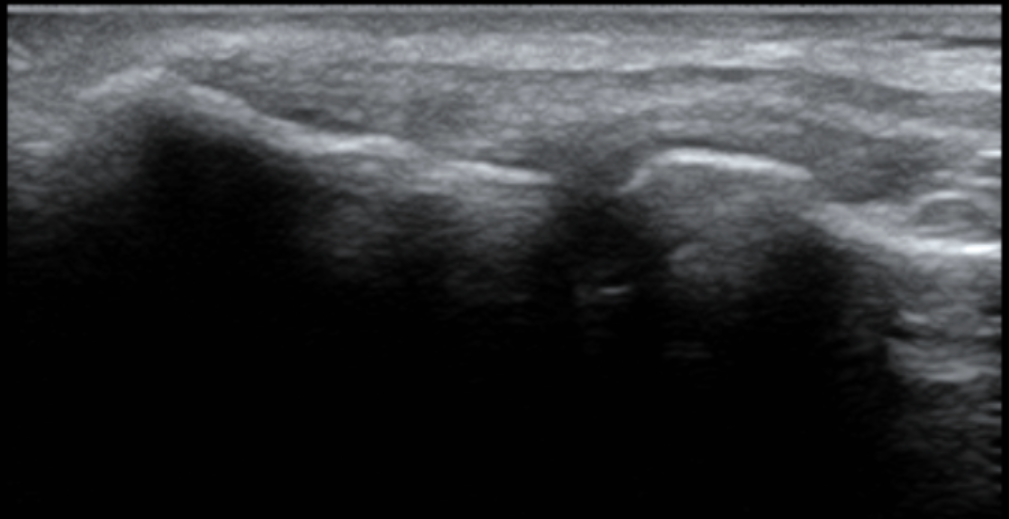

1. Understanding Structural Changes: Normal vs. Irregular Using MSK Ultrasound, we can visualize the state of your tendons and bones in real-time.

Normal Elbow (Left): The bone contour is smooth, and the tendon is attached firmly with a uniform texture.

Irregular Elbow (Right - Patient Case): Chronic inflammation can lead to bone surface irregularities or "bone spurs." As seen in the image, the bone line is no longer smooth, which can cause constant irritation to the surrounding tissues.